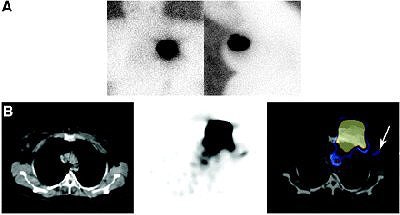

| Negative planar imaging and positive SPECT/CT identification of hot node in 64-year-old overweight patient (BMI, 29.1 kg/m²). (A) Anterior and left lateral planar images of chest obtained with 57Co flood. Except for uptake at injection site, no hot spot was identified. (B) SPECT/CT transaxial images. CT, SPECT, and fused images are shown from left to right. Hot node was detected at level I of left axilla (arrow), in keeping with SN. Increased uptake detected in left mediastinum appears to be non-nodal uptake in blood vessel. Copyright © by the Society of Nuclear Medicine Inc. |